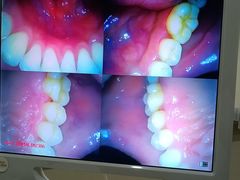

• 土豆口腔(凤凰北总店)

• -土豆口腔(凤凰北总店)

一只酷酷的螃蟹 | 24-10-26